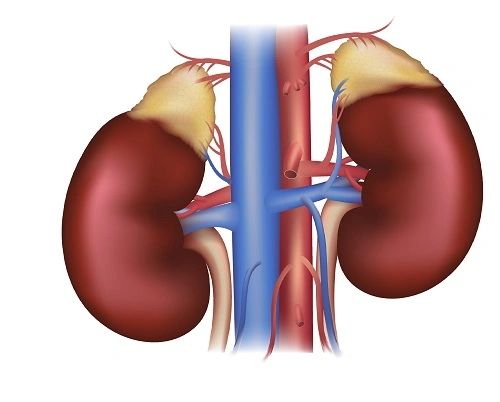

There are two kidneys in the human body, each is fist-sized, and both are located in the abdomen, on either side of the spine, right behind the rib cage (Fig. 1). They span from T12 to L3. Each kidney is approximately three vertebrae in length. When interpreting radiographs, this can be operated to assess any change in size. The right kidney is observed somewhat lower due to the influence of the liver (Fig. 2). The body's circulation is cleared of water-soluble wastes by the kidneys, which act to keep blood pressure, pH levels, electrolyte concentrations, and the quantity of extracellular fluid, and consequently they maintain homeostasis in the body. Urea and uric acid are the main waste products managed by the urinary system. When these products are excessively piled up, severe diseases occur. Blood is purified through filtration, reabsorption, and secretion. These processes are accomplished by the nephrons in each kidney (Fig. 3). There are thousands of nephrons in the kidneys; each is supported by a filtration mechanism called the renal corpuscle, containing a glomerulus and a Bowman's capsule. To evaluate how well the kidneys are working, the glomerular filtration rate is examined. Kidneys are designed with external and internal structures.

Kidneys are responsible for ejecting surplus quantities of salt in blood, filtering them out into urine, in a way that can adjust its quantities in blood. Regulating blood pressure is among the crucial functions performed by the kidneys. Also, renin is an enzyme naturally produced by these organs. It works not only to regulate blood pressure and electrolyte balance through stimulating a variety of hormones, but also to convert blood protein into angiotensin, a hormone produced due to the fall of blood pressure. The top of the kidneys includes the adrenal glands (Fig. 9) which are in turn stimulated to release another substance known as aldosterone, a hormone allowing the reabsorption of more salt and water into the blood. Blood volume is accordingly elevated, and subsequently blood pressure.